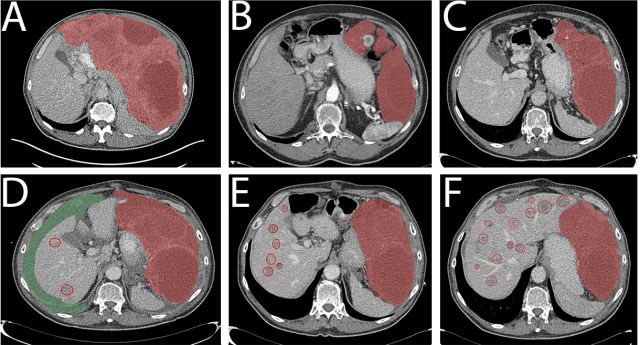

病例1为一个76岁的老年男性,腹部巨大包块(29cm,图1A)),ECOG 3,穿刺证实为GIST,PDGFRα外显子18突变 (NM_006206.5: c.2531_2542del; p.(M844-S847del))。一线给予伊马替尼400mg qd,一周后恶心症状就缓解了,并且生活质量明显改善。治疗持续了1年,最佳疗效为SD(每3月CT评估)。随之腹膜出现了新病灶(图1B),第15个月时调整为二线治疗药物索坦 37.5mg qd。病情在服药后1年内得到良好控制(图1C)。1年后出现PD,中等量腹水(图1D)。经过引流后症状控制,肝脏出现多发转移灶并行穿刺活检,调整为三线药物瑞戈非尼(160mg qd, 3/4方案),PFS为5个月(图1E),并于PD停药后1月死亡(图1F),重新口服伊马替尼无效。患者在三线瑞戈非尼和四线伊马替尼治疗期间留取了血样,发现在1E和1F期间突变拷贝数增加(180-850拷贝/ml,图3A),最后一次随访(死亡前2周)时拷贝数达到4767拷贝/ml。

图1. 病例1的CT图像

病例2为76岁的老年女性,因腹痛就诊,CT发现腹腔25cm的肿块伴多发肝转移(图2A和2B),肝穿刺活检提示CD117阳性GIST,突变分析未发现KIT突变,PDGFRα当时未检测。 一线给予伊马替尼400mg qd,10天后临床症状缓解,耐受性良好,3个月后获得PR(图2C 和2D),30个月后原发肿瘤和肝转移灶都出现了PD(图2E和2F)。重新分析原来标本的PDGFRα发现外显子18突变 (NM_006206.5: c.2527_2538del; p.(I843_ D846del))。患者接受了增量的伊马替尼(400mg BID),耐受性良好,但未获得疗效 (3个月后的CT评估,如图2G和2H)。随后调整为索坦37.5mg qd,但2个月后症状持续恶化,OS总共36个月。 由于组织标本采集困难,本例患者进行了血样的ctDNA分析(图3B) ,结果显示患者在伊马替尼治疗的第16.5个月时突变拷贝为6拷贝/ml,这个低水平一直维持到第30个月。在伊马替尼增量开始时为275拷贝/ml,第33个月增长为852拷贝/ml,索坦治疗启动后,一度降至208拷贝/ml,但因患者在第36个月死亡未再收集血样。

图2. 病例2的CT图像